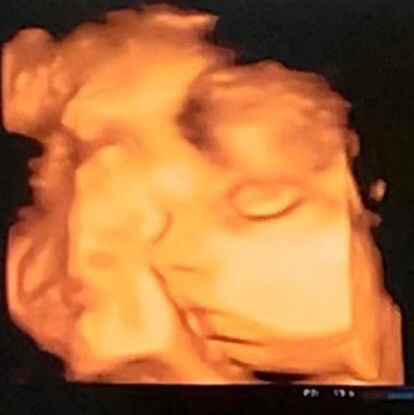

MasyaaAllah Tabarakallah, USG usia kandungan 34w2d dedek malu-malu nutupin tangannya ke muka sebelah, jadi mommy cuman bisa lihat dari samping doang, udah di toel toel tetep gakmau ngadep depan 🤭 HPL 22 November Baby Girl#firstmom